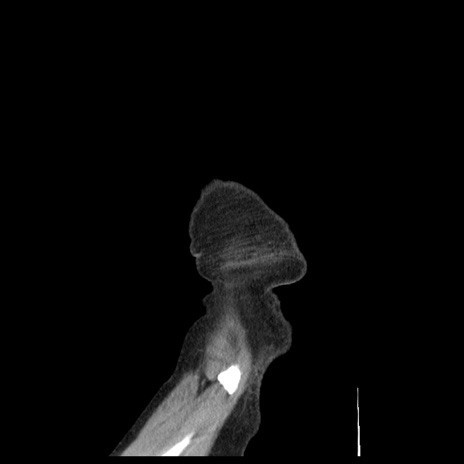

症例

【症例】80歳代女性

【主訴】腹痛

【現病歴】8時間前から腹痛あり来院。

【既往歴】糖尿病、脂質異常症、子宮体癌にて子宮全摘術

【身体所見】意識清明・会話良好だが腹痛で苦悶様、全腹部にわたって反跳痛と圧痛あり

【データ】WBC 13600、CRP 0.14、LDH 224、CK 90